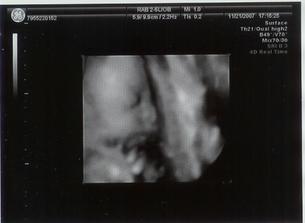

21.11.2007 jsme byly na 3D,4D UTZ mame cca 1296g a malá vůbec nespolupracovala proste spala ----- 4.1.2008 tak mame cca 2001g ----- 18.1.2008 kontrola dopadla dobře otvirame se jak máme ----- 25.1.2008 další kontrola -----tak kontrola se nekonala misto ni se narodila mala v 37+6tt v 6:17 vážila 2520g a měřila 46cm ____________________________________________________________________________________________________________________________________________________